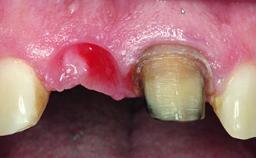

Replacement of a Compromised Upper Right Central Incisor: Hard- and Soft-tissue Augmentation, Late Placement of an RC Bone Level Implant

A 36-year-old male patient with a compromised maxillary central incisor was referred by his general dentist for consultation. The patient’s chief complaints were the gradual debonding of a temporary crown on the right central incisor and unsatisfactory esthetics due to an increasing diastema between the right central and lateral incisors. The patient reported a traumatic event some years previously, when a crown had been placed after root-canal treatment. The referring dentist wanted to provide a new crown restoration, but was concerned about the condition of the residual root. Anamnesis was negative for any other dental or periodontal pathology in the remaining dentition. The patient reported taking no medications: He was a smoker (10 to 15 cigs/day) and had realistic esthetic expectations.